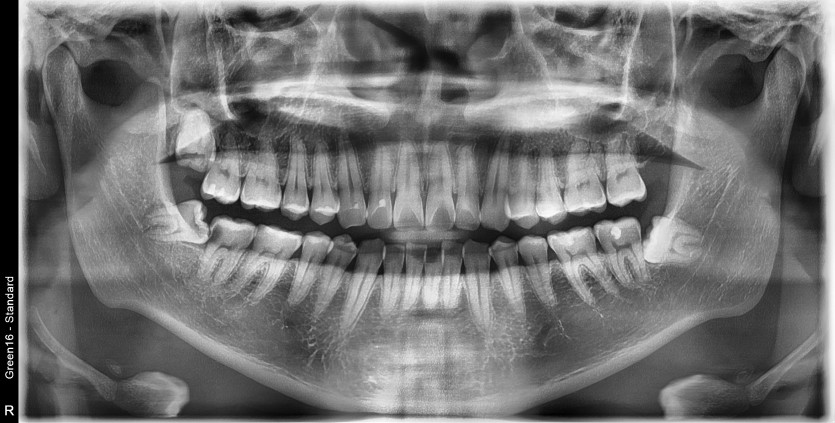

#48 사랑니 발치

구강외과 전문의가 당일 발치했습니다.